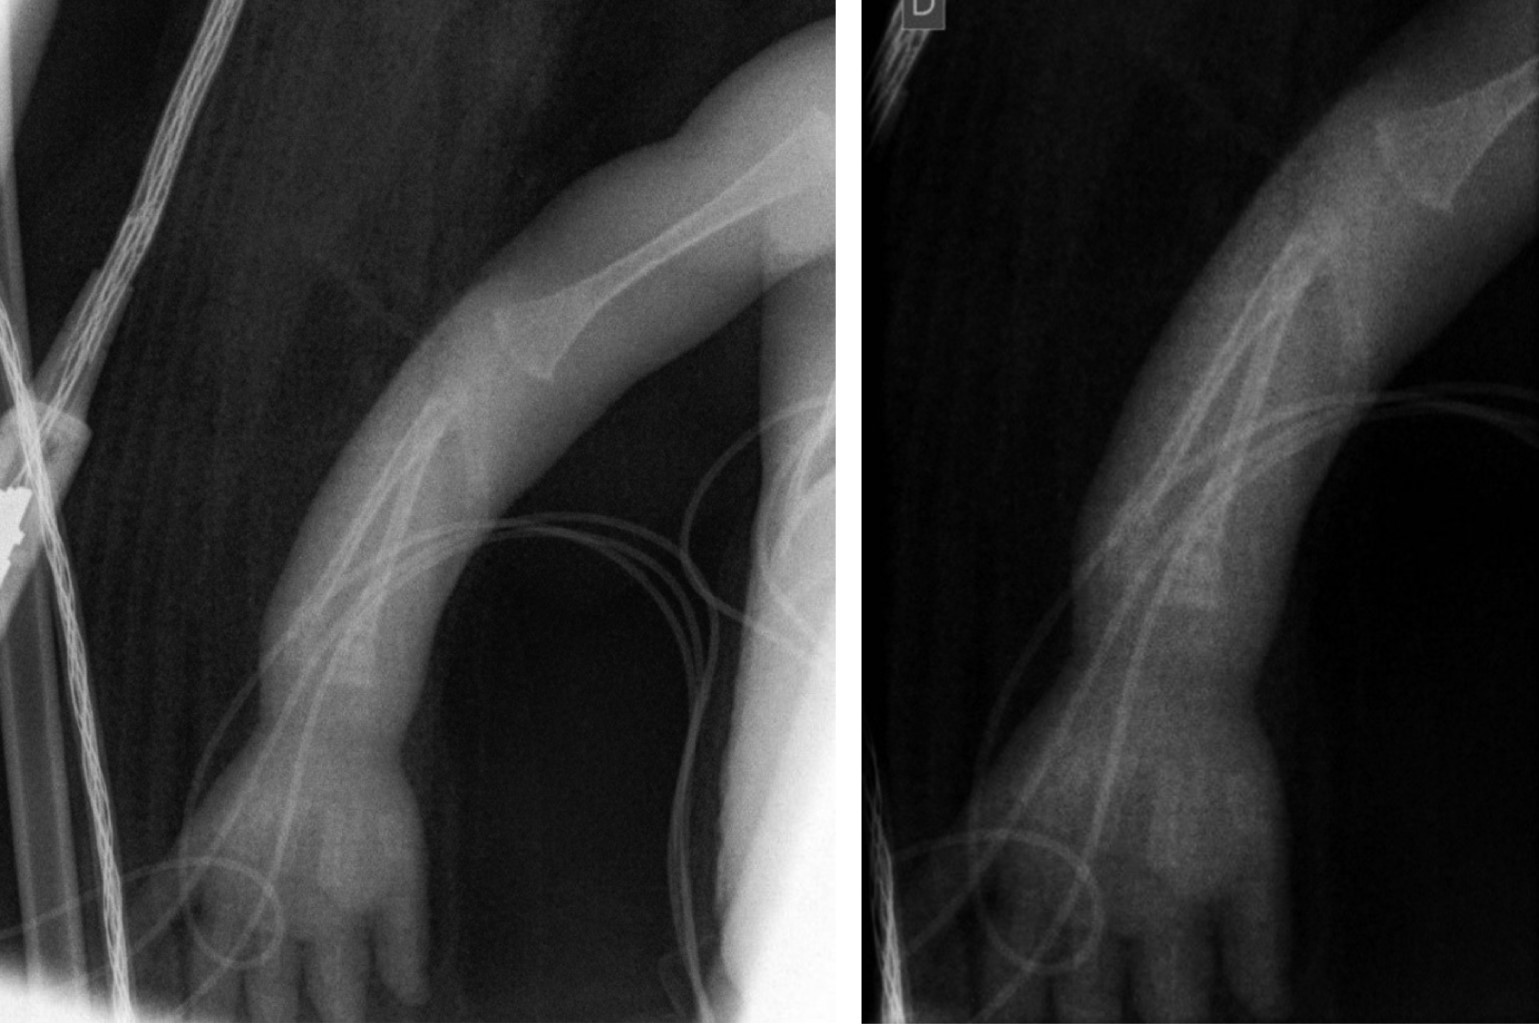

Distal radius and ulna fracture in a premature neonate with osteopenia

A preterm 29 +2-week-old baby with low birth weight and a complicated inmediate neonatal period. At six postnatal weeks, deformity and swollen arm was observed with no trauma associated. Radiographs of her forearm showed a distal radius and ulna fracture. Conservative management was decided by observation and careful handling of the patient. The patient was subsequently found to have osteopenia of prematurity. High clinical suspicion is required in with osteopenia of prematurity. This case highlights the importance of treating osteopenia of prematurity properly and careful handling of these patients. Even so, the prognosis for these fractures is excellent.

Figure 1